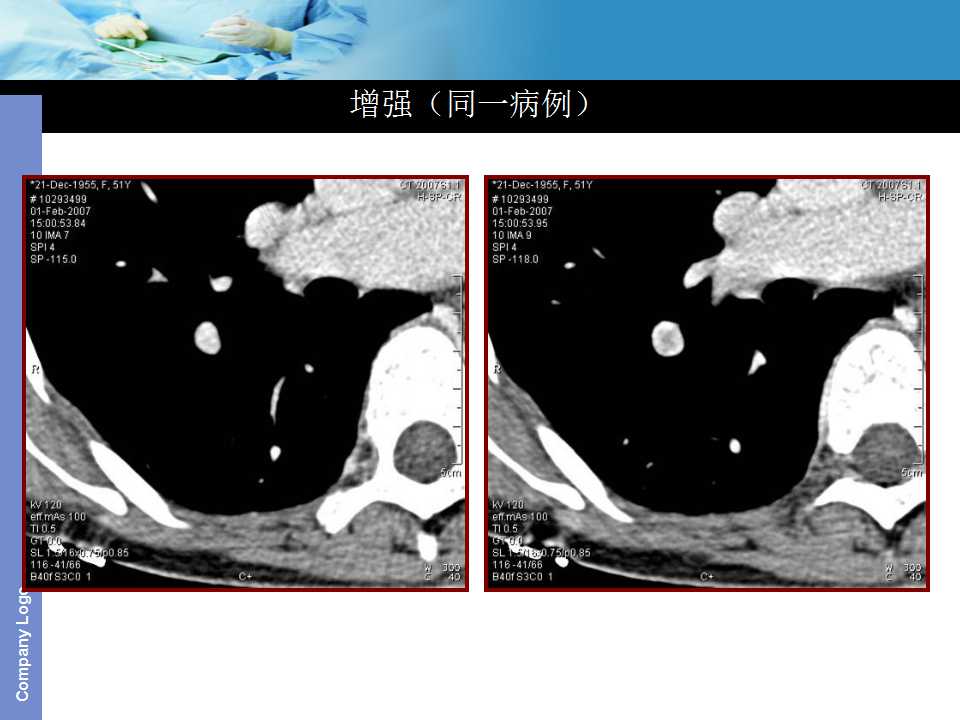

肺癌影像诊断